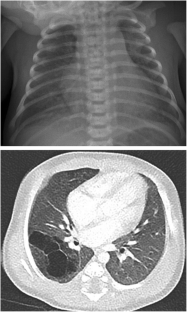

Fig. 1